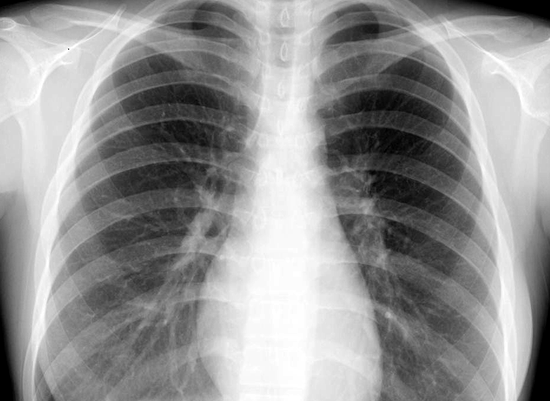

呼吸器科は間質性肺炎の治療薬「オフェブ」の副作用で腎臓機能が低下しているので治療薬を一時中止している。「オフェブ」の服用を止めたので下痢も無くなり、すこぶる体調が良くなっているが・・・「オフェブ」飲まなければ肺機能が悪化する、飲めば腎臓が悪化する。どうすべきか?あと一か月服用を止めて様子を見ることになった。今のところ間質性肺炎の進行は止まっているようだがこれからどうなるかなぁ~?